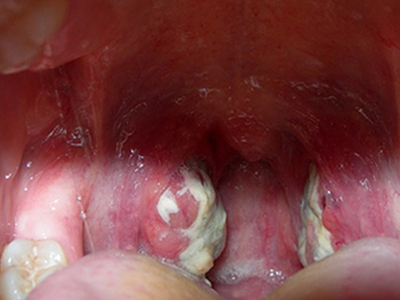

扁桃体结石是指发生在扁桃体隐窝的结石,是扁桃体隐窝细胞聚集所致的灰白色钙化团,扁桃体结石临床较少见。

扁桃体结石多呈灰白色,表面粗糙,质地坚硬。部分患者可自觉咽部有异物,结石较大者,进食可出现阻挡感。并发扁桃体炎症时,可出现患侧扁桃体肿大、咽痒、刺激性咳嗽等症状,甚则可出现咽喉肿痛、吞咽困难、发热等全身症状。

扁桃体内可发现灰白色、质地较硬的细小沙石,或可在肿大的扁桃体内触及较硬的肿块,触时有微痛感。